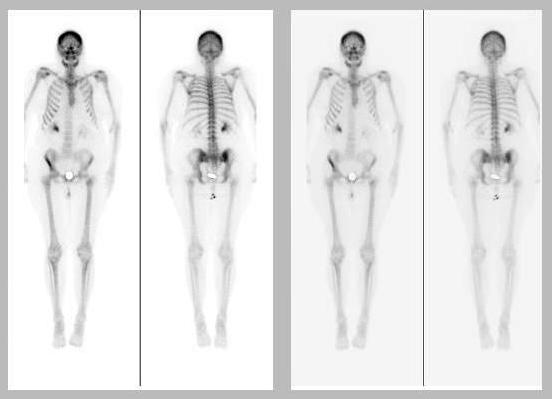

The patient is a 66-year-old female with history of non-Hodgkin's lymphoma involving the cervical lymph nodes and the bone marrow, status post chemotherapy. The patient was found to have bone involvement and underwent radiation therapy of the thoracic spine.

There is markedly increased tracer uptake within the right anterior iliac wing extending from the anterior/superior iliac spine to rim of the acetabular roof. There is also increased tracer uptake adjacent to the right SI joint. There is subtle mild increased tracer uptake within the proximal left femur at the region of the intertrochanteric line. There is increased tracer uptake within the mandible that is fairly symmetric in appearance with a focal area of photopenia at the apex of the mandible. The axial and proximal appendicular skeleton demonstrates mild but diffuse increased tracer uptake. Incidentally, there is splaying of the left lower ribs posteriorly.

2. Mild and diffuse increased tracer uptake within the proximal appendicular and axial skeleton as well as in the rami of the mandible, likely representing a reactive bone marrow process secondary to chemotherapy.